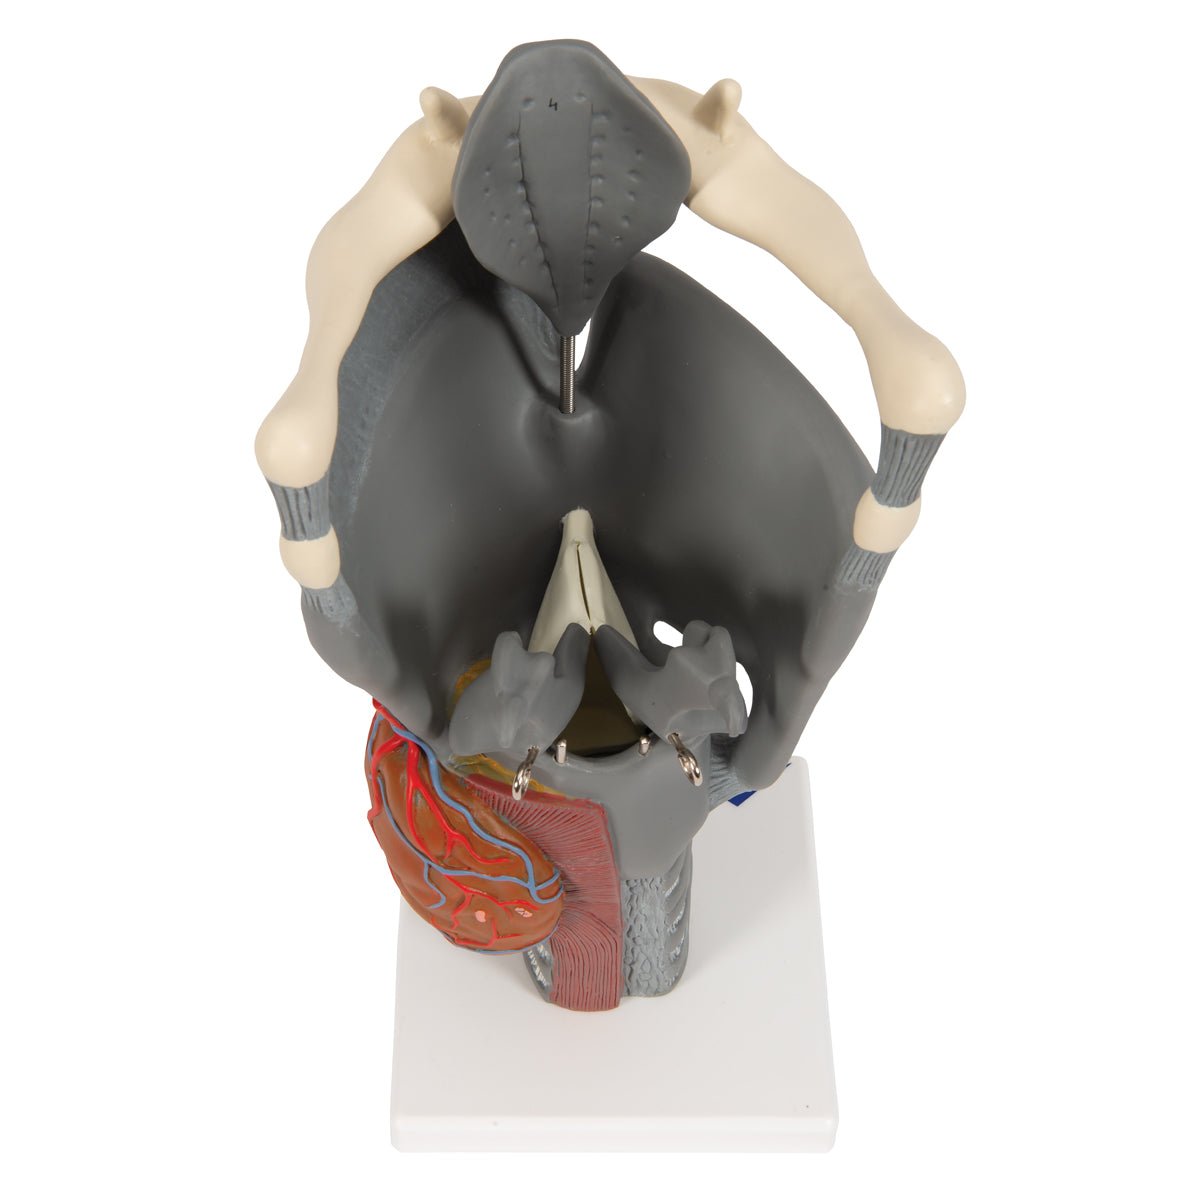

Anatomical models

Selling anatomical models is the mainstay of eAnatomi, although we also spend a lot of resources developing our own anatomical materials such as posters. Anatomical models are used for various purposes and can show both defined tissues, organs and organ systems. Are you looking for a simple model of bone tissue or perhaps an advanced torso model based on MRI technology, you can find it all at eanatomi.com.